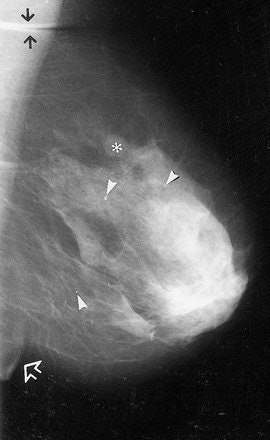

Standard negative mammograms: 1965-1975. Standard examination included a 90° lateral and craniocaudal (CC) view of each breast. Lateral (above) and CC (below) direct-exposure film mammograms. There was only slight (if any) compression of the breast during exposure, which impaired depiction of tissues close to the chest wall because the x-ray beam could not effectively penetrate these thicker regions of the breast without grossly overexposing the thinner regions close to the nipple. Sickles EA, "Breast Imaging: from 1965 to the present," Radiology 2000; 215:1-16.